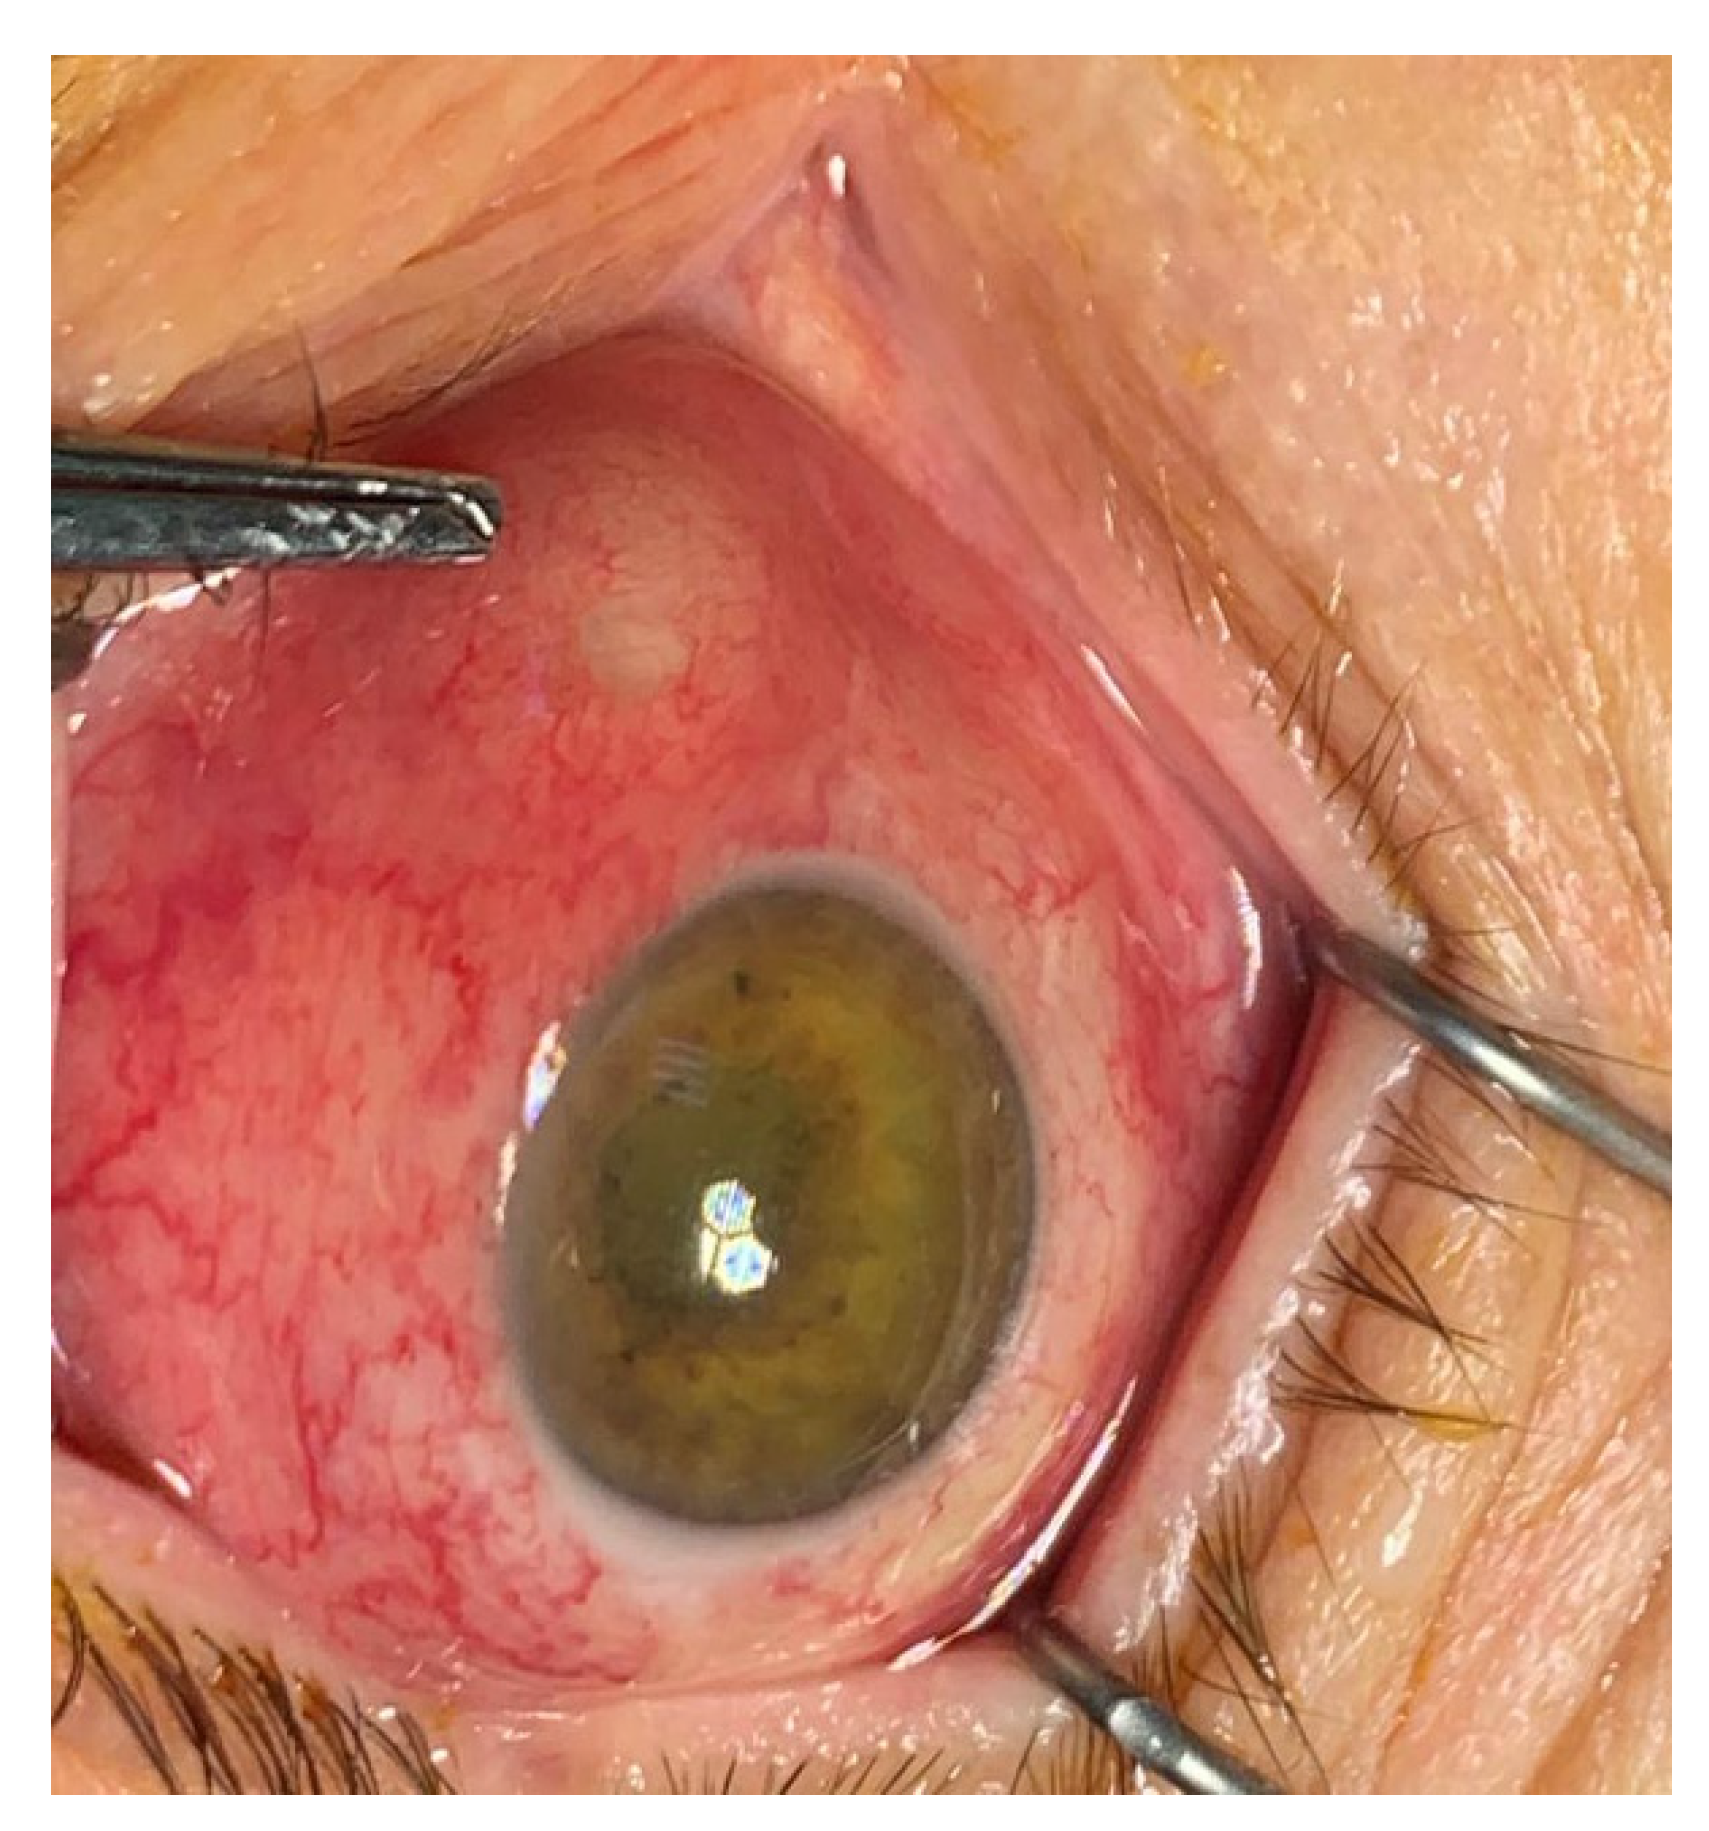

Figure 2.

Endogenous hvKp endophthalmitis (EKE): corneal haze, intense hyperemia, scleral abscess in the internal angle, with impending ocular perforation (archive of the Ophthalmology Department, Emergency University Hospital Bucharest).